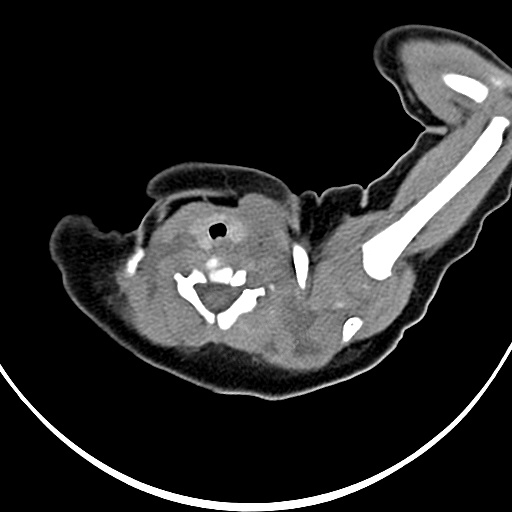

标题: PED1779:左侧锁骨下方异常密度影 请指教 [打印本页]

患者,男,1月,出生后一月,无明显诱因出现颈部左前方肿块。体检:左侧颈部轻度凸起包块,触之较硬。

病灶与左侧胸锁乳突肌分界不清,软组织密度,不似囊性改变,从病人的年龄及病变性状首先要除外先天性斜颈(肌性斜颈)可能。

左侧胸锁乳突肌肿大,考虑产伤所致

胸锁乳突肌挛缩(斜颈)?